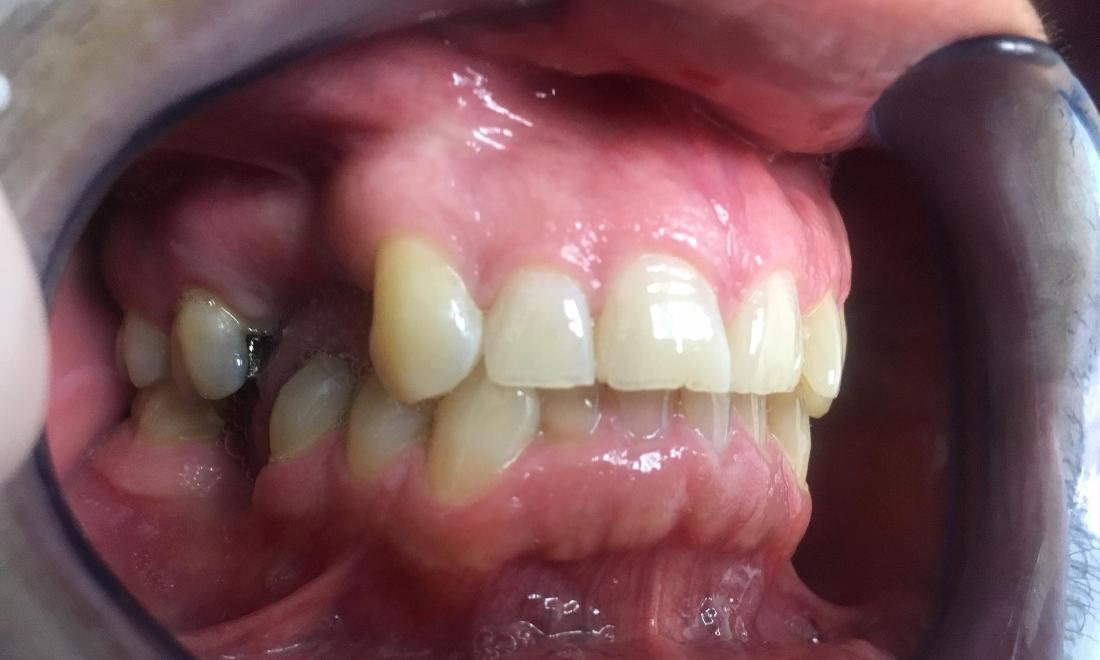

This patient was suffering from multiple areas of missing teeth. The patient was not a candidate for dental implants due to severe bone loss in the area. We utilized fixed bridges to replace multiple missing teeth in just 2 visits.